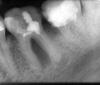

Kolobok Опубликовано 29 марта, 2010 Поделиться Опубликовано 29 марта, 2010 Здравствуйте! Два года назад был пульпит 7 нижнего зуба. 9 месяцев назад стал болеть от горячего.Пошел к врачу, сделали рентген, со слов врача пустые каналы. 3 раза закладывали какое-то лекарство, ходил неделю с временной пломбой, потом как сказал врач были запломбированы каналы, поставлена постоянная пломба.3 месяца назад делал рентген другого зуба (нижний 6), посокльку он болел. 7 зуб сейчас никак не беспокоит, но есть вопрос: хорошо ли запломбированы в нем каналы ? Ссылка на комментарий

Vareнька Опубликовано 29 марта, 2010 Поделиться Опубликовано 29 марта, 2010 (изменено) Здравствуйте! Два года назад был пульпит 7 нижнего зуба. 9 месяцев назад стал болеть от горячего.Пошел к врачу, сделали рентген, со слов врача пустые каналы. 3 раза закладывали какое-то лекарство, ходил неделю с временной пломбой, потом как сказал врач были запломбированы каналы, поставлена постоянная пломба.3 месяца назад делал рентген другого зуба (нижний 6), посокльку он болел. 7 зуб сейчас никак не беспокоит, но есть вопрос: хорошо ли запломбированы в нем каналы ?Ни на одном из Ваших снимков я не вижу качественной пломбировки каналов. Изменено 29 марта, 2010 пользователем Vareнька Ссылка на комментарий

Ксения А Опубликовано 29 марта, 2010 Поделиться Опубликовано 29 марта, 2010 Необходимо перелечить корневые каналы у 6 и 7. Ссылка на комментарий